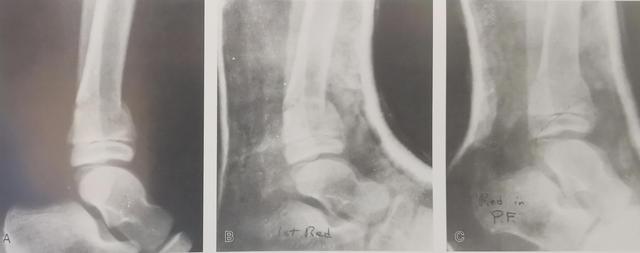

Lockwood-Wilkins关于儿童骨折的临床专著收录了一名7岁儿童胫骨远端骨折,建议石膏固定应采用跖屈位。

足底屈曲位石膏固定

一名7岁儿童胫骨远端骨折,侧位x光片显示轻微后屈畸形。b .起初患儿在踝关节中立位制动,但反向畸形加重,于是取下石膏,将踝关节固定在跖屈位。c .将儿童踝关节固定在跖屈位,这是这类骨折的正确固定位置。